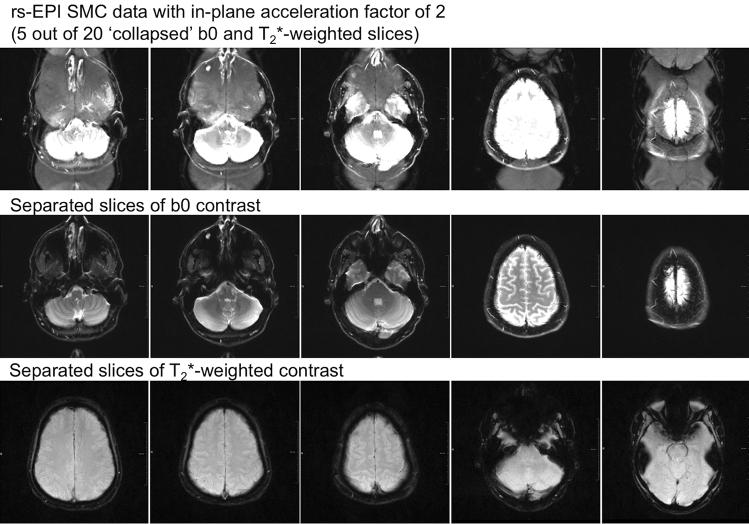

High-resolution, navigator-corrected, diffusion-weighted imaging was performed simultaneously with T*-weighted acquisition at 3 T in a phantom and in five healthy subjects using an adapted readout-segmented EPI sequence (rs-EPI).

The results demonstrated that simultaneous acquisition of two contrasts (here diffusion-weighted imaging and T*-weighting) with SMC imaging is feasible with robust separation of contrasts and minimal effect on image quality.

在一个体模和五名健康受试者中,使用经过改良的读出分段 EPI 序列(rs-EPI),在 3T 上进行高分辨率、导航校正、扩散加权成像,同时进行 T*-加权采集。

结果表明,SMC 成像同时采集两种对比度(此处为扩散加权成像和 T*-加权)是可行的,对比度分离稳健,对图像质量的影响最小。